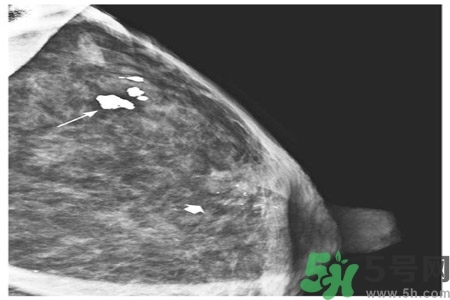

乳腺鈣化點(diǎn)是指可以在乳房造影片上看到鈣沉積物。乳房鈣化點(diǎn)有兩種類型:大鈣化作用和微鈣化作用。

大鈣化作用通常是乳房?jī)?nèi)部的退行性改變,形成原因多是由于曾經(jīng)有損傷、發(fā)炎,或乳房動(dòng)脈的老化,并且通常與癌癥無關(guān)。

微鈣化作用是可能在迅速分解細(xì)胞的部位找到的鈣斑點(diǎn)。這些由迅速分解細(xì)胞留下的殘余物可以顯示為微鈣化作用。當(dāng)它們成群大量出現(xiàn)時(shí),即表示有小腫瘤的可能。

乳腺癌近幾年的發(fā)病率居高不下,女性朋友特別到了25歲之后,每年都要定期檢查乳房,已便及早發(fā)現(xiàn)疾病,盡快治療。醫(yī)院常用檢測(cè)乳腺癌的方法是采用乳腺鉬靶檢查,而診斷為乳腺鈣化的情況在這種檢查中顯示率也相當(dāng)?shù)母摺?/p>

乳腺鈣化是指可以在乳房造影看到鈣沉淀物,有多種因素可導(dǎo)致乳腺鈣化,如組織退變、壞死鈣鹽沉積,某些腫瘤分泌含鈣鹽的物質(zhì),使血管周圍組織鈣化。分析鈣化的形態(tài)、數(shù)目、部位以及與周圍結(jié)構(gòu)的關(guān)系,對(duì)辨別病變的性質(zhì)有較大的幫助。